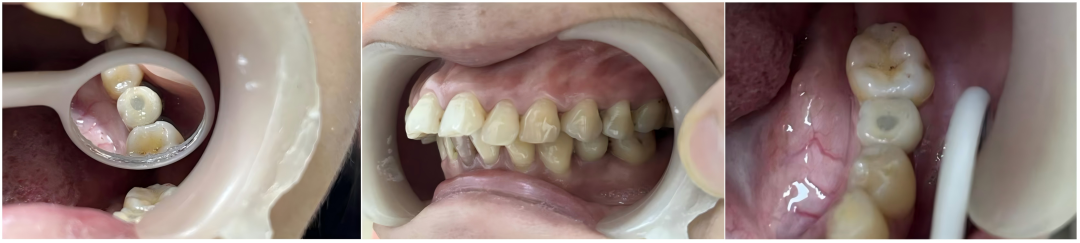

2024年5月19日,在中山市口腔医院专家的主刀下,神湾医院首例口腔种植手术成功完成!这不仅实现了神湾医院种植牙技术“零的突破”,更标志着神湾镇的居民们,从此在家门口就能享受到市级医院水平的种植牙服务!截至目前,已有近百名牙列缺损的患者在神湾医院,“足不出镇”,由市口腔医院牙齿种植的专家亲自操刀,彻底告别遗留已久的缺牙烦恼。实现“高质量、高效率、高品质”的医疗服务体验。

不同缺牙位点种植体X线影像

种植患者1年后口内复查照片及X线影像